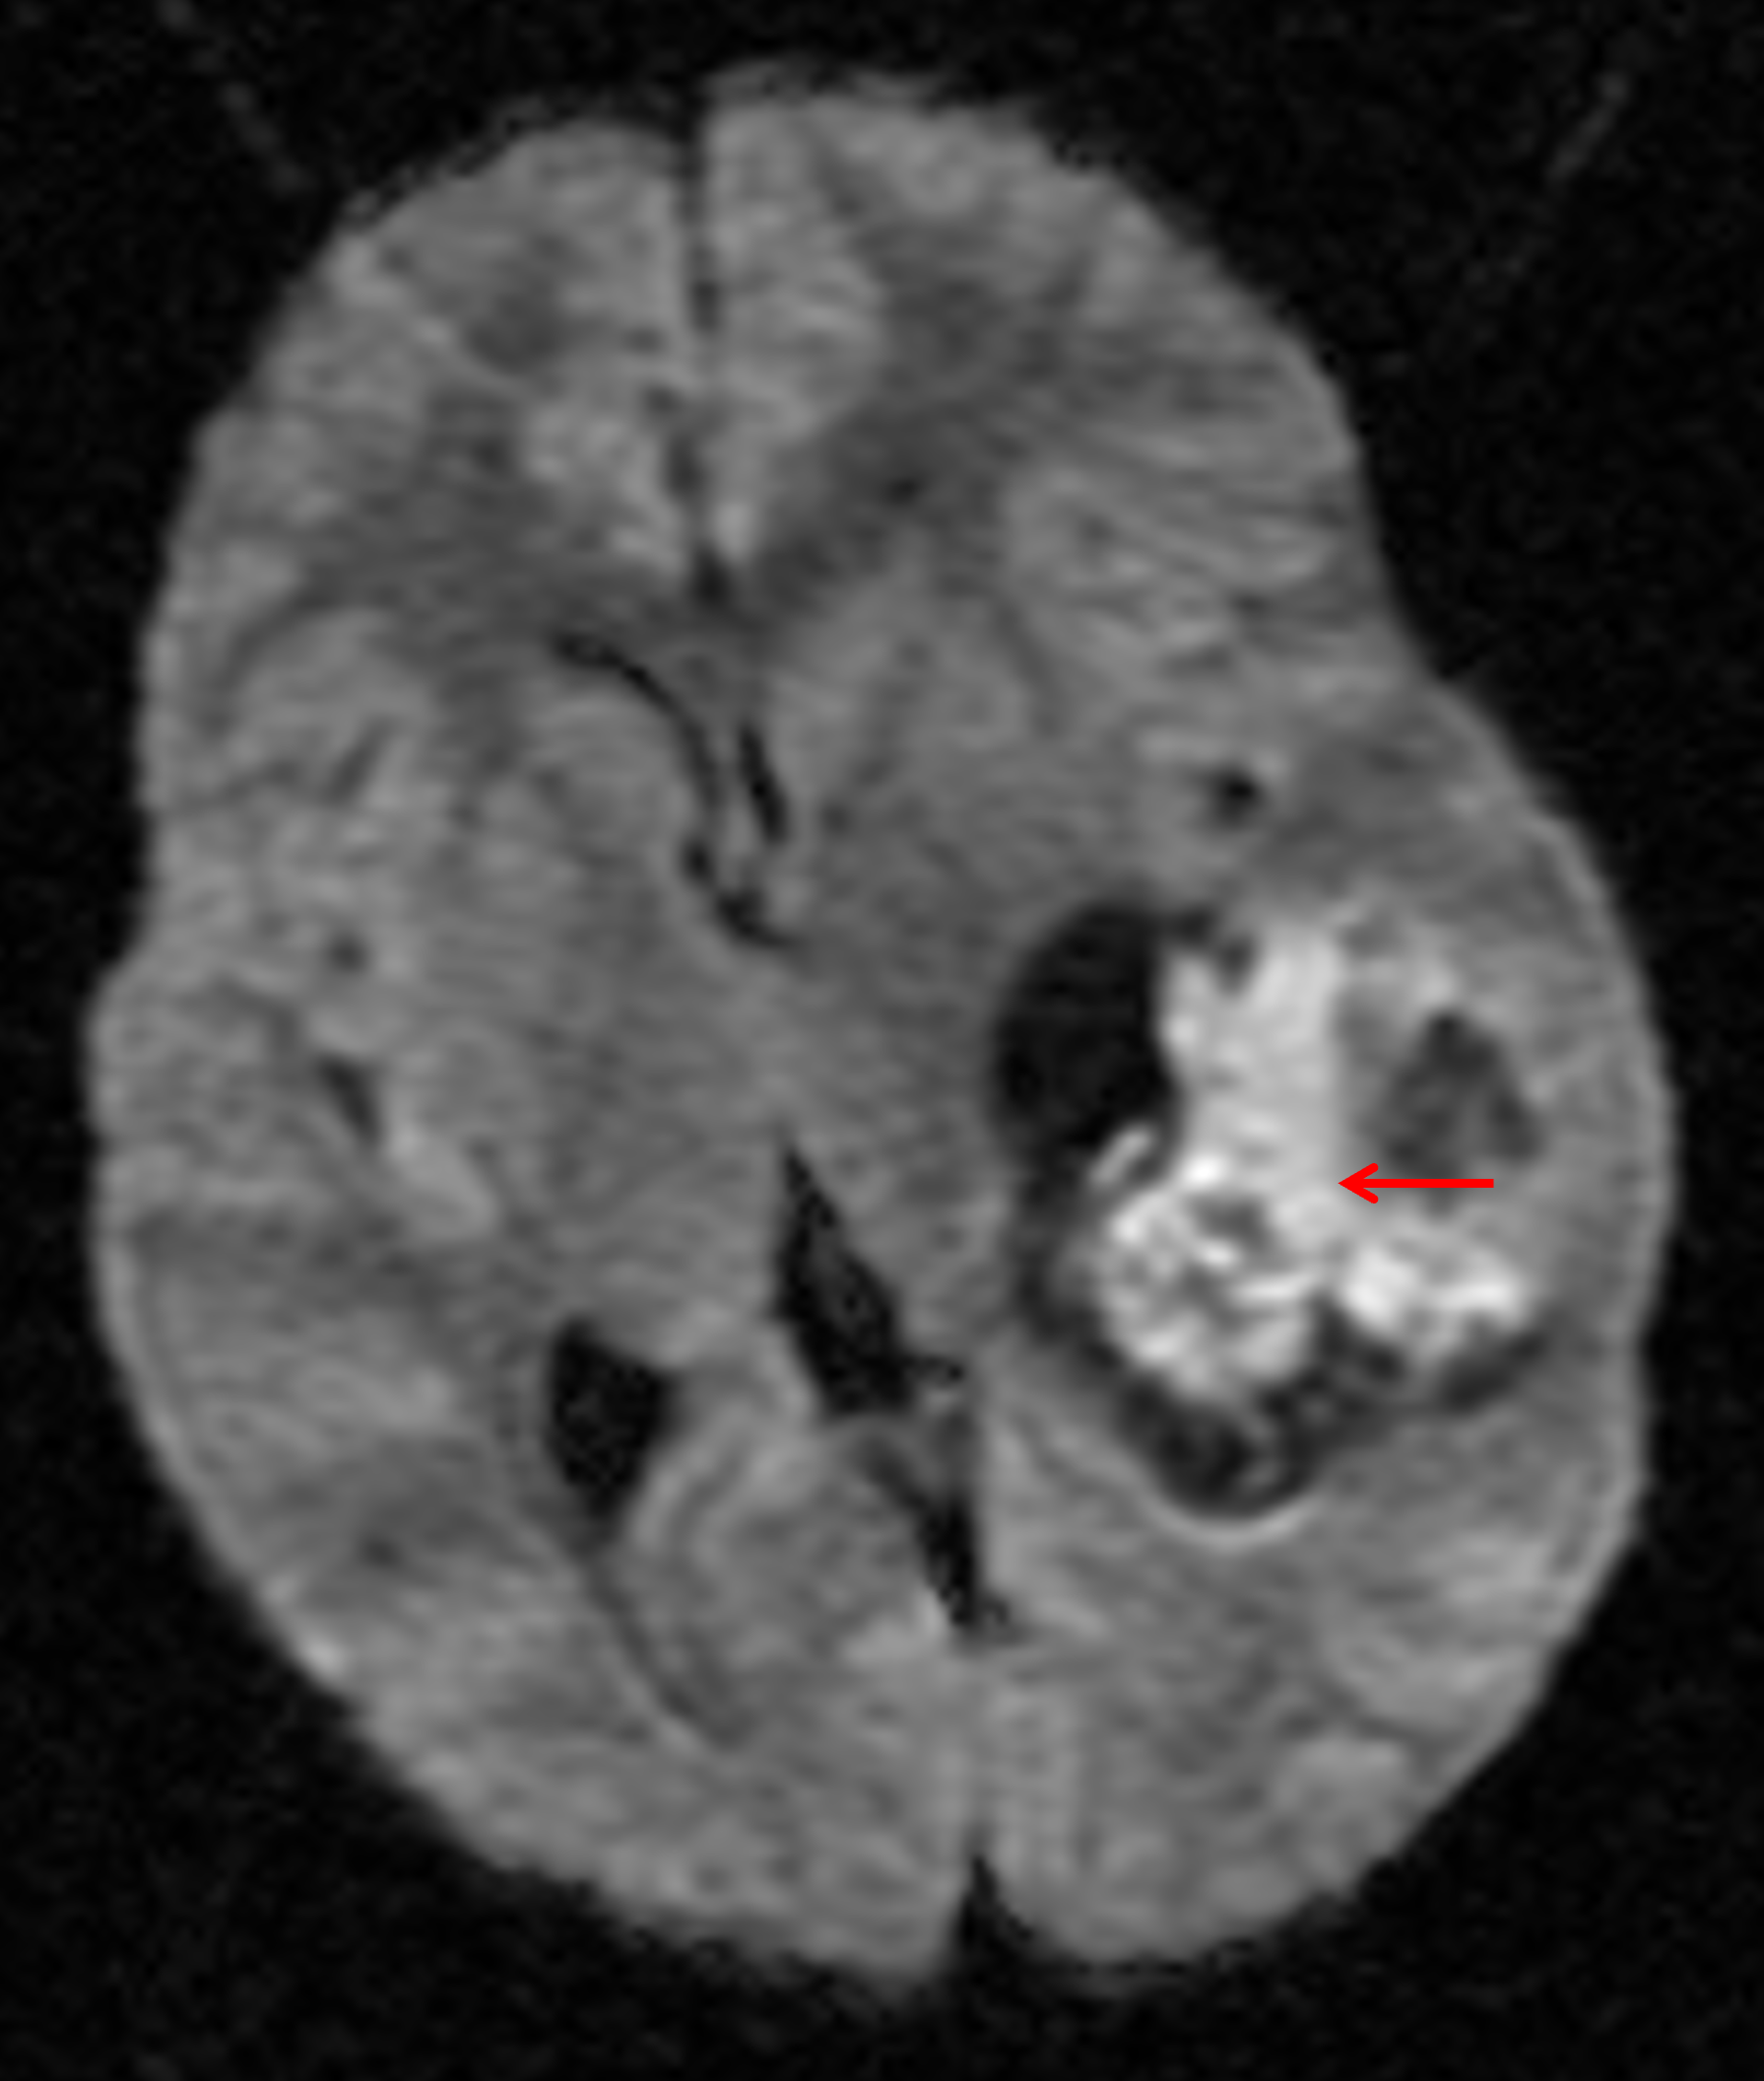

Age: 3

Sex: Male

Indication: Speaking difficulty, imbalance

Atypical teratoid/rhabdoid tumor (AT/RT)